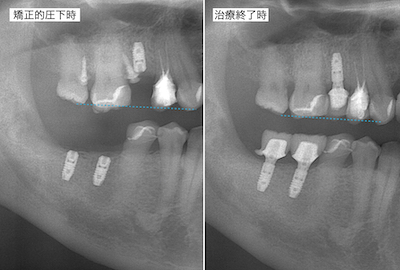

右上のアンカースクリューによる圧下の結果のレントゲンです。